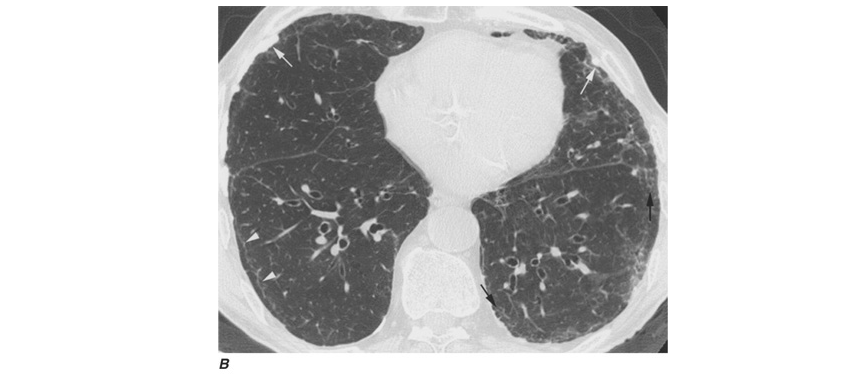

Workers heavily exposed through sandblasting in confined spaces, tunneling through rock with a high quartz content (15–25%), or the manufacture of abrasive soaps may develop acute silicosis with as little as 10 months of exposure. The clinical and pathologic features of acute silicosis are similar to those of pulmonary alveolar proteinosis . The chest radiograph may show profuse miliary infiltration or consolidation, and there is a characteristic HRCT pattern known as “crazy paving” (Fig. H-2). The disease may be quite severe and progressive despite the discontinuation of exposure. Whole-lung lavage may provide symptomatic relief and slow the progression.